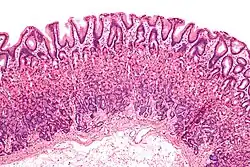

Mucosa gástrica a baixa ampliação.

O tecido epitelial é constituído por células compactas, com pouco espaço intercelular, e ligadas entre si por moléculas de adesão celular. As células epiteliais podem ser escamosas, cubóides ou colunares e assentam sobre uma lâmina basal. Esta lâmina é a camada superior da membana basal, sendo a inferior a lâmina reticular que se encontra na proximidade do tecido conjuntivo na matriz extracelular segregada pelas células epiteliais.[18]

Existem vários tipos diferentes de tecido epitelial, o qual se encontra modificado de modo a corresponder a uma função em particular. No trato respiratório encontra-se um tipo de revestimento epitelial ciliado. No revestimento epitelial do intestino delgado existem microvilos, enquanto no do intestino grosso existem vilosidades intestinais. A pele que reveste o corpo dos vertebrados é constituída por uma camada exterior de epitélio escamoso estratificado e queratinizado, enquanto 95% das células da epiderme são queratinócitos.[19] As células epiteliais na superfície exterior do corpo geralmente segregam matriz extracelular na forma de uma cutícula. Em animais mais simples isto pode ser apenas um revestimento de glicoproteínas.[15] Em animais mais avançados, formam-se glândulas nas células epiteliais.[20]